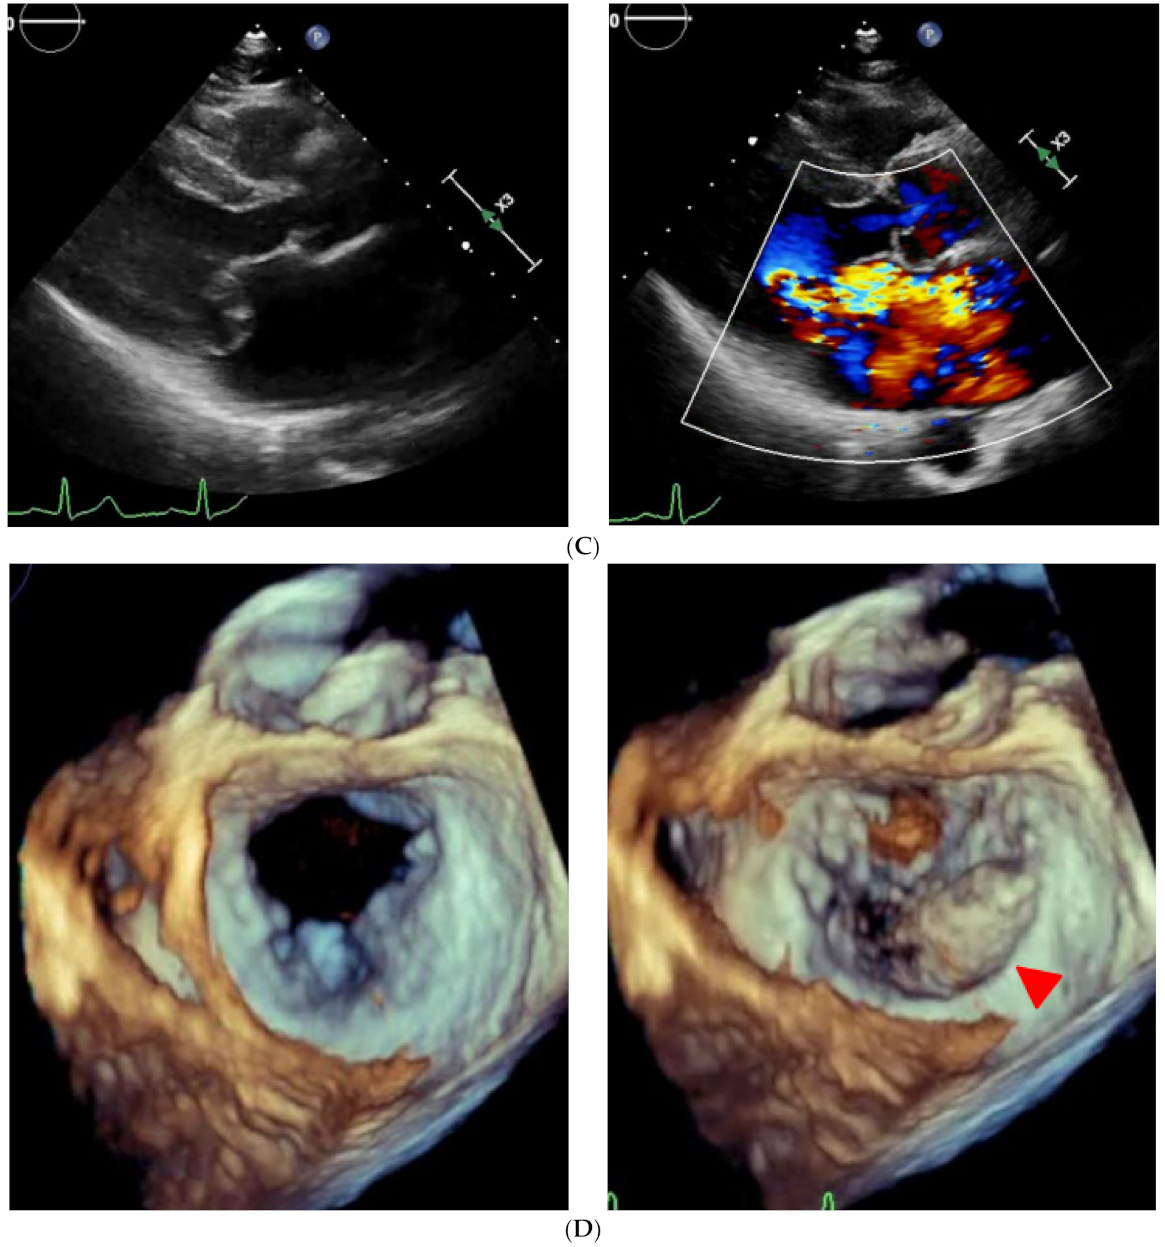

2.2. On Admission

2.3. In-Hospital Course